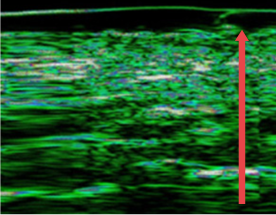

ปรับปรุงชั้นหนังแท้ของผิวหนังที่บางลงเนื่องจากความชรา การทำหัตถการผิวบ่อยๆ และการกระตุ้นจากภายนอก

ก่อนฉีด

หลังฉีด 4 เดือน

(ชั้นหนังแท้หนาขึ้น 12%)

หลังฉีด 7 เดือน

(ชั้นหนังแท้หนาขึ้น 27% )